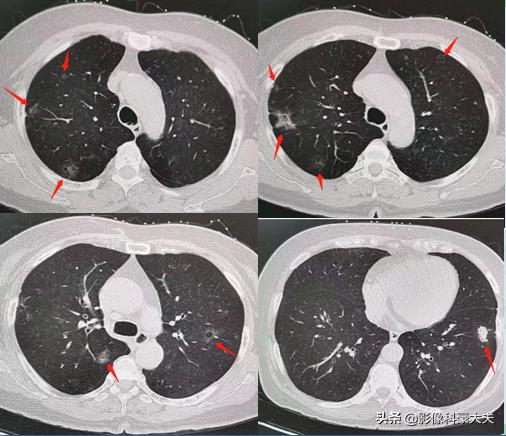

上图是我们今年遇到的另一例多原发肺癌,患者为54岁女性,有肺癌家族史。